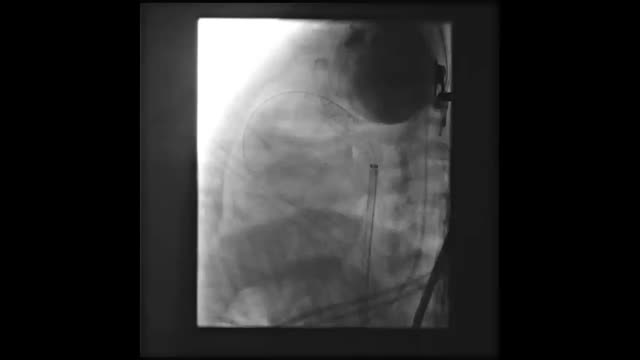

We present the case of a boy aged 15 months with a prenatal diagnosis of pulmonary atresia with intact ventricular septum who underwent pulmonary valve perforation and balloon valvuloplasty with an 8 mm balloon at 9 days post birth (Fig. 1A–D; Appendix B, videos 1–3). At 30 days, due to persistent desaturation, the decision was made to perform percutaneous ductal stenting, since this was less invasive compared to other techniques used to increase pulmonary flow. The procedure, guided by ultrasound, consisted in the delivery, via the left femoral artery and using a 5 F introducer, of a drug-eluting stent (Onyx Frontier, Medtronic, USA) measuring 4.5 × 12 mm to the ductus arteriosus (Fig. 1E and F; Appendix B, videos 4 and 5). Five days after the procedure, the patient experienced vomiting, and the abdominal ultrasound scan used for initial assessment revealed a mass in the left groin, with subsequent Doppler and angio-CT scans allowing visualization of a pseudoaneurysm at the level of the left common iliac artery (Fig. 2A–F).

(A) and (B) Right ventriculogram, anteroposterior and lateral views showing pulmonary valve atresia (7.5 mm ring). C) Pulmonary valvuloplasty performed with a TYSHAK MINI® (NuMED) 8 × 20 mm balloon catheter advanced on a 0.0014 coronary guidewire, which traversed the ductus arteriosus to the aorta supported by a gooseneck snare. (D) Angiographic confirmation of preserved pulmonary flow after valvuloplasty. (E) Lateral aortogram showing patent ductus arteriosus and filling of right chambers. (F) Aortogram following stent placement.